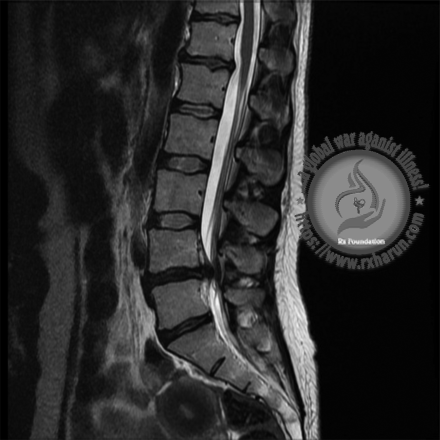

- Magnetic resonance imaging (MRI) scan – which uses magnetic fields and computers to produce three-dimensional images of your spine.